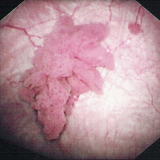

③内視鏡(膀胱鏡)検査

診断には不可欠な検査です。腫瘍が認められた場合、組織型、異型度診断のために生検(腫瘍の一部分を採集)を行うことがあります。

④内視鏡検査(腎盂尿管ファイバー)

直接腎盂尿管内を観察し、生検による組織検査を行います。